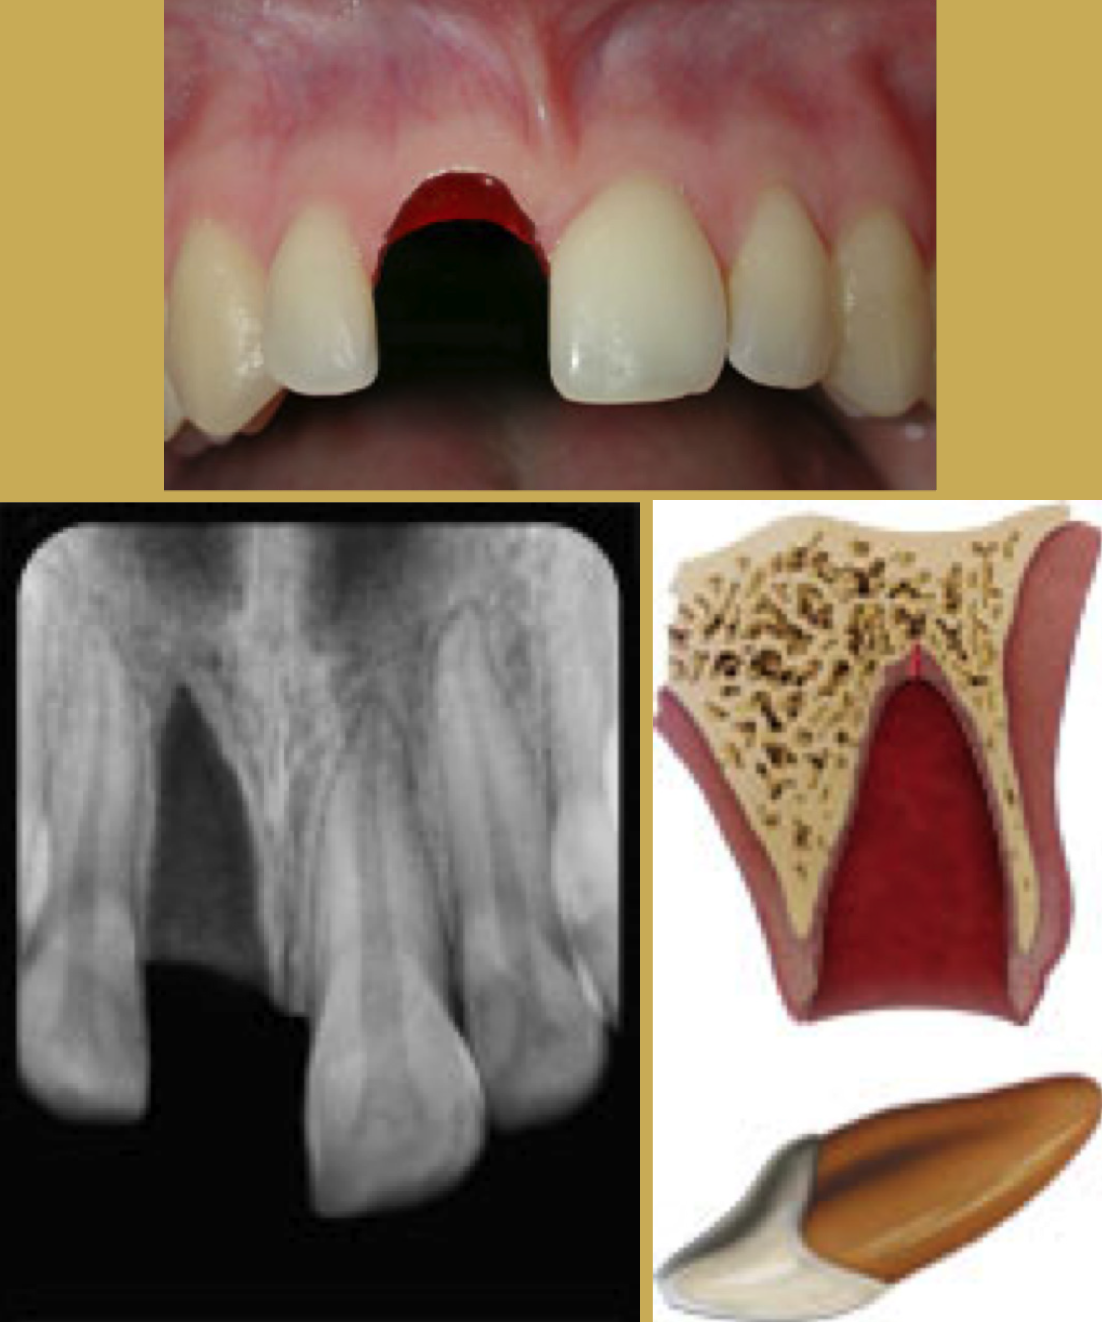

TMJ Injuries

Most blows to the mandible do not result in fractures, yet significant force can be transmitted to the temporomandibular disc and supporting structures that may result in permanent injury (Figure 1 and Figure 2). In both mild and severe trauma, the condyle can be forced posteriorly to the extent that the retrodiscal tissues are compressed. Inflammation and edema can result forcing the mandibular condyle forward and down in acute malocclusion. Occasionally this trauma will cause intracapsular bleeding, which could lead to ankylosis of the joint.

Fig 1. TMJ Landmarks

Figure 1

Fig 2. Dimensional Image of TMJ

Figure 2